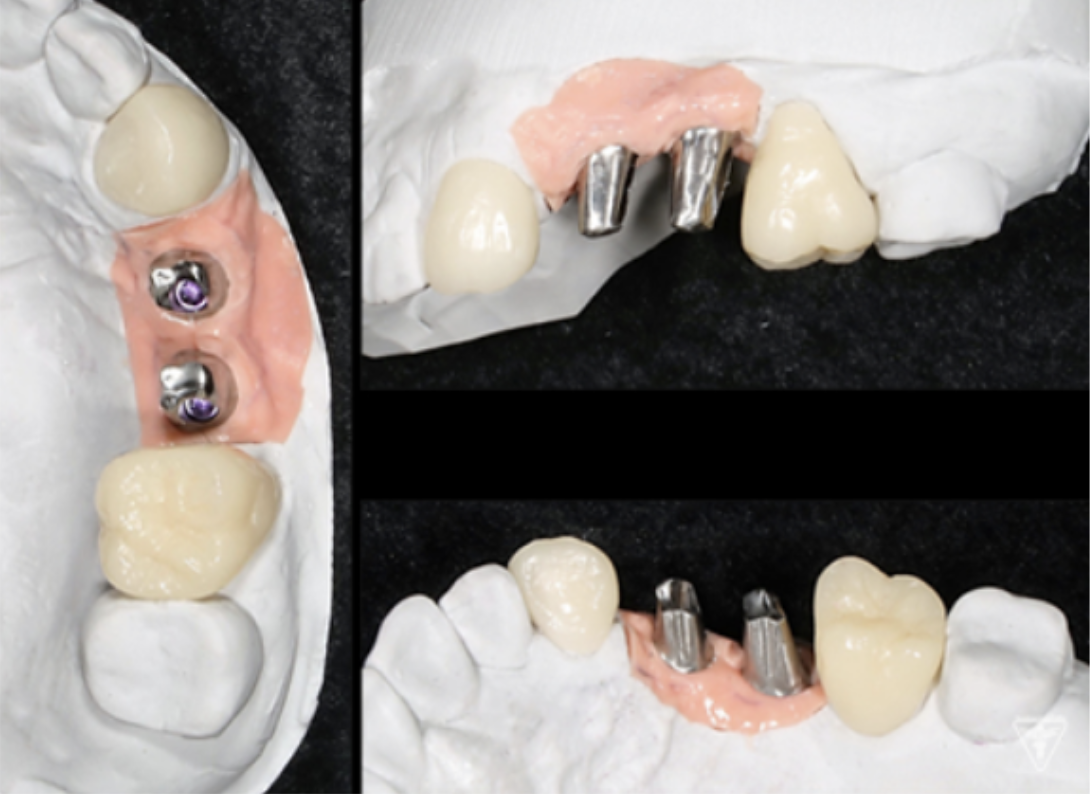

インプラント

サージカルガイドの作成